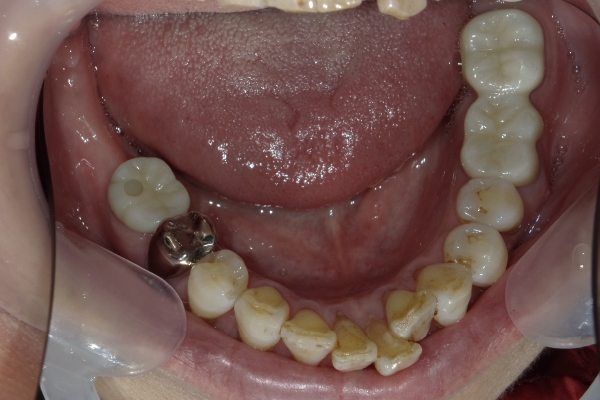

Case2

| 主訴 | 右側でも物を噛めるようにしてほしい |

|---|---|

| 治療期間 | 約3か月 |

| 治療費 | 900,000円 |

| 治療内容 | 右下に2本のインプラントを入れ、上の被せ物は3本分入れました。右でもしっかり食事ができるようになり、やって良かったとおっしゃっていました。 |

| 治療の リスク | インプラントも残っている歯と同様に歯周病になる可能性がある |